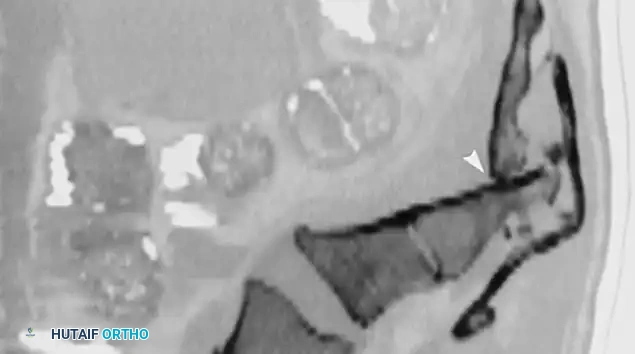

A

B

C

Fig. 35-62 A, Sagittal CT scan of transverse fracture through S3 resulting in transection of sacral nerve roots (arrow) . B, MRI of sacral fracture resulting in complete canal compromise. C, Postoperative CT scan shows decompression of sacral spinal canal after laminectomy (arrows) .